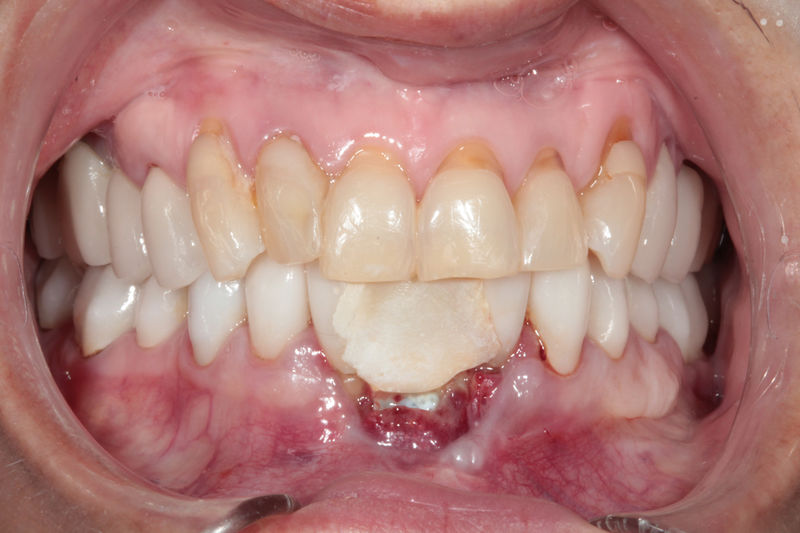

Implante fracasado, extracción, carillas, coronas y prótesis fija.